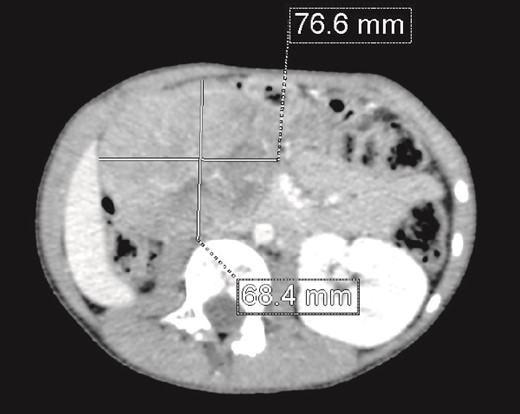

We present the case of an 8-year-old boy with no significant medical history and no prenatal diagnosis of congenital renal malformation. During a physical examination following a minor abdominal injury sustained while playing, a right flank abdominal mass was discovered. Clinically, the patient’s general condition was stable. The mass was non-tender, firm, and fixed to deep planes while mobile over superficial planes. There was no evidence of varicocele. Abdominal ultrasonography and computed tomography (CT) revealed a well-circumscribed, well-encapsulated solid mass measuring 9 × 6 cm, with areas of necrosis. The mass was located in the right kidney, in contact with the cephalic portion of the pancreas and closely abutting the inferior vena cava, which was displaced to the left. The right kidney was not visualized, and no secondary lesions were detected (Fig. 1). Magnetic resonance imaging (MRI) was performed to further characterize the tumor’s origin. However, it confirmed only the presence of the tumor and the absence of normal renal parenchyma, providing no additional information regarding the origin of the upper right abdominal quadrant mass (Fig. 2). Given the unclear origin of the tumor, a CT-guided biopsy was performed. Pathological analysis of the biopsy revealed nephroblastoma without signs of anaplasia. The patient was subsequently treated with neoadjuvant chemotherapy, consisting of vincristine and actinomycin D for 4 weeks, following the SIOP 2001 protocol, and was scheduled for nephrectomy. Post-chemotherapy CT evaluation demonstrated a 75% reduction in the size of the right kidney mass (Fig. 3). The patient underwent an open nephrectomy. Intraoperatively, an atretic ureter was identified, with no visible normal renal parenchyma. An extended right nephrectomy was performed (Fig. 4a and b).

CT scan: A solid mass of 9 × 6 cm of diameter containing some areas of necrosis, well circumscribed, well encapsulated at the expense of the right kidney in contact with the cephalic portion of the pancreas and in close contact with the inferior vena cava, which is pushed to the left. The right kidney is not visualized.